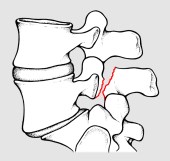

Per spondilolisi si intende l’interruzione di quella parte dell’arco posteriore vertebrale compresa fra le due apofisi articolari (fig 1). Se bilaterale, essa può favorire lo scivolamento in avanti di una vertebra rispetto a quella sottostante, realizzando così la spondilolistesi (fig 2).